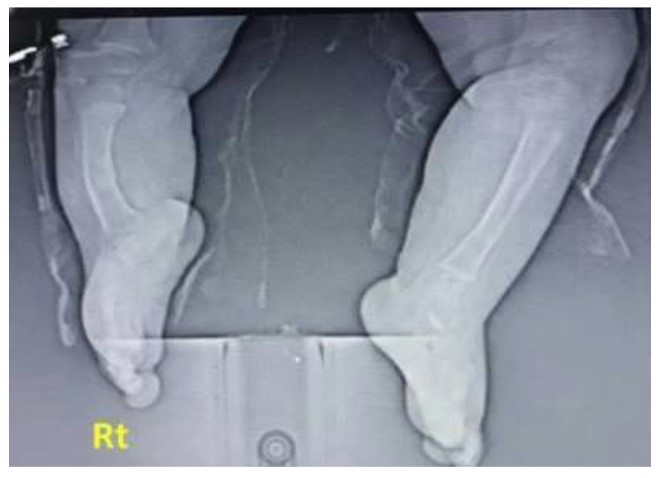

X-ray posteroanterior projection of both Rt and Lt legs; the Rt leg is shortened with thickened bowing of tibial bone, thickened cortex borders, and irregular bony marrow trabeculation compared with the normal Lt leg. Fibula is absent, associated with a hypoplastic, deformed attachment of the distal tibia to the ankle region, and later showing irregular hypoplastic carpal bony fusion.